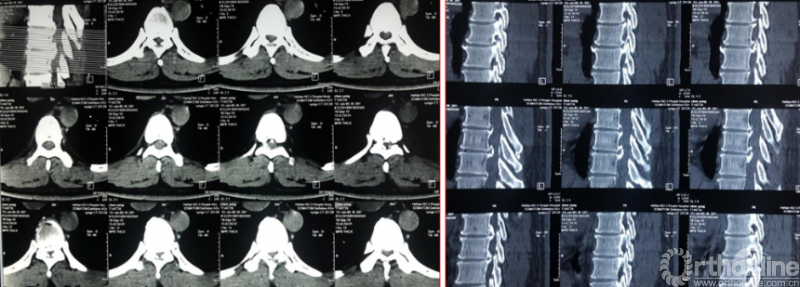

术前资料

术中资料